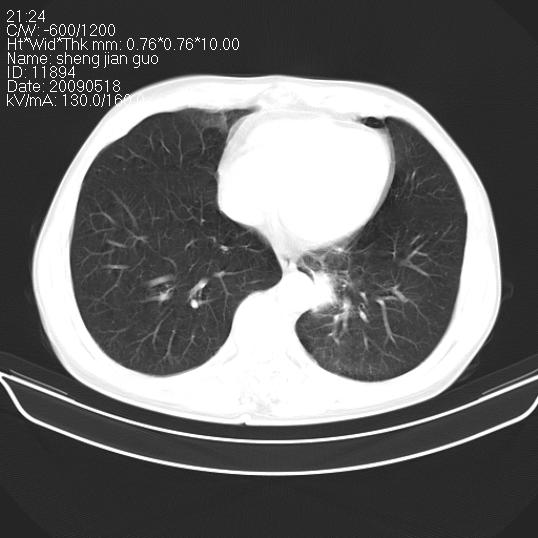

以下是引用zjzjr在2009-5-19 17:25:00的发言:[br]支持楼主考虑,另左肺下叶阻塞性炎症。

以下是引用zhao_bin2008在2009-5-19 17:48:00的发言:[br]支持左肺下叶周围型肺癌并阻塞性肺炎。

以下是引用杀毒软件在2009-5-19 17:36:00的发言:[br]支持楼主

以下是引用zsl6918在2009-5-20 7:10:00的发言:[br]左侧中心型肺癌!